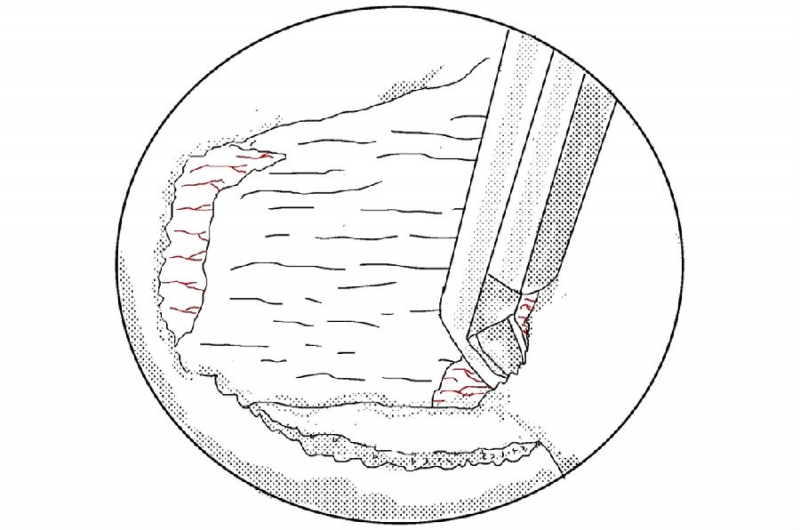

10. 剥离黄韧带;

11. 用UBE拉钩牵开神经根;

12. 突出间盘表面的预止血和神经根周围束带的切除;

13. 使用髓核钳摘除突出的髓核组织;

14. 你可以选择使用等离子电凝皱缩来缩小裂口;

15. 或者是纤维环缝合修复;

16. 在手术最后放置引流是好习惯,最好放置于椎板表面,不至于干扰神经根。